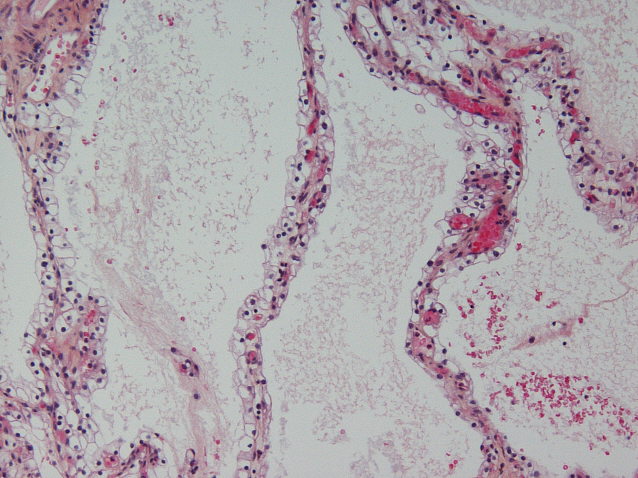

Renal tumor grading

Case ID: 593